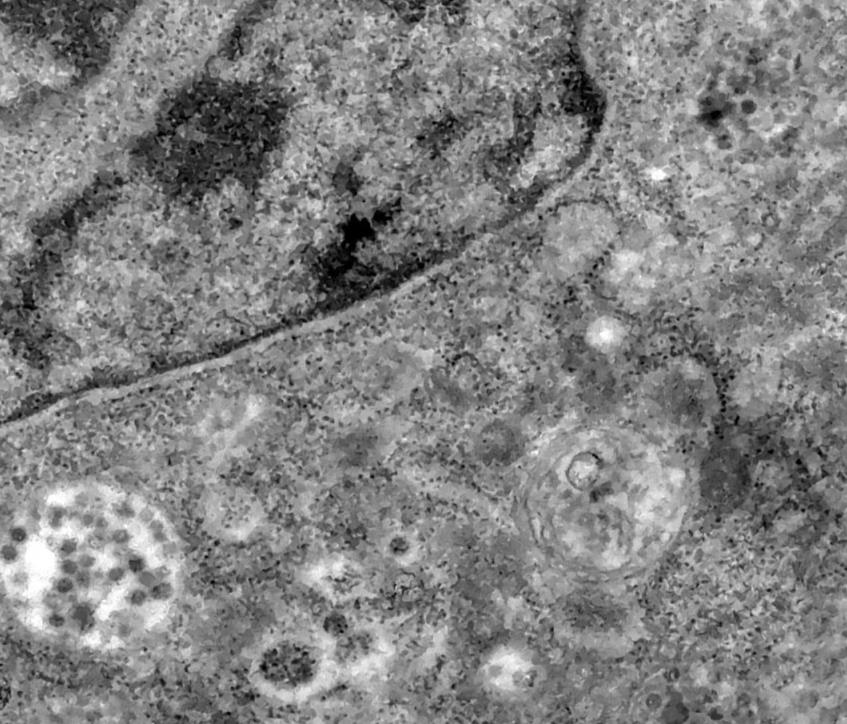

据telegraph报道,近日,拉丁美洲最大的医学研究中心的科学家们用“镜头”捕捉到了冠状病毒感染正常细胞的整个过程。

据悉,这些照片是在巴西Oswaldo Cruz基金会(Fiocruz)的专家研究Sars-CoV-2病毒复制时拍摄到的,拍摄工具是一种可以将物体放大200万倍的高科技设备——透射式电子显微镜,这组照片详细记录了冠状病毒感染正常细胞的过程。

如图所示,照片里的黑点实际上就是病毒颗粒,这些病毒正在试图感染并进入细胞的细胞质(细胞质内就是细胞核,而细胞核内含有遗传物质)。

Fiocruz在一份声明中宣称,实验中使用的细胞不是人类的,而是从非洲绿猴身上分离出来的。据悉,这组照片有助于世界各地的科学家们更好地了解新冠病毒,并有助于他们开发能够终结这场大流行的疫苗和治疗方法。